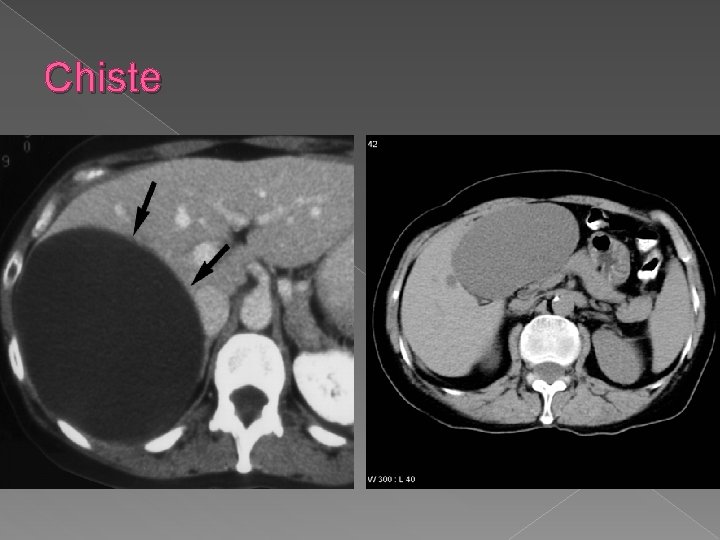

Chiste

Computer tomografia Tehnica: -sectiuni contigui de 8 -10 mm, 5 mm pentru hil si cai biliare -nativ +contrast: cu rol in diferentierea leziunilor de parenchimul normal q Leziunile focale • Sunt de regula spontan hipodense • Incarcare mai mica decat a parenchimului hepatic Exemple: v Tumori hepatice-primitive sau secundare v Chiste; v Abcese; v Hematoame; v Steatoza.